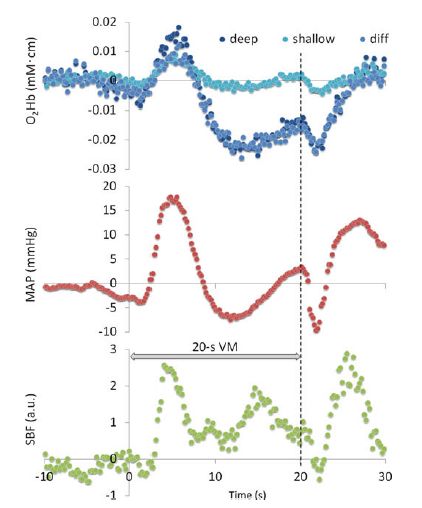

Tsubaki A, Kojima S, Furusawa AA, Onishi H.: Effect of valsalva maneuver-induced hemodynamic changes on brain near-infrared spectroscopy measurements.Adv Exp Med Biol. 2013;789:97-103